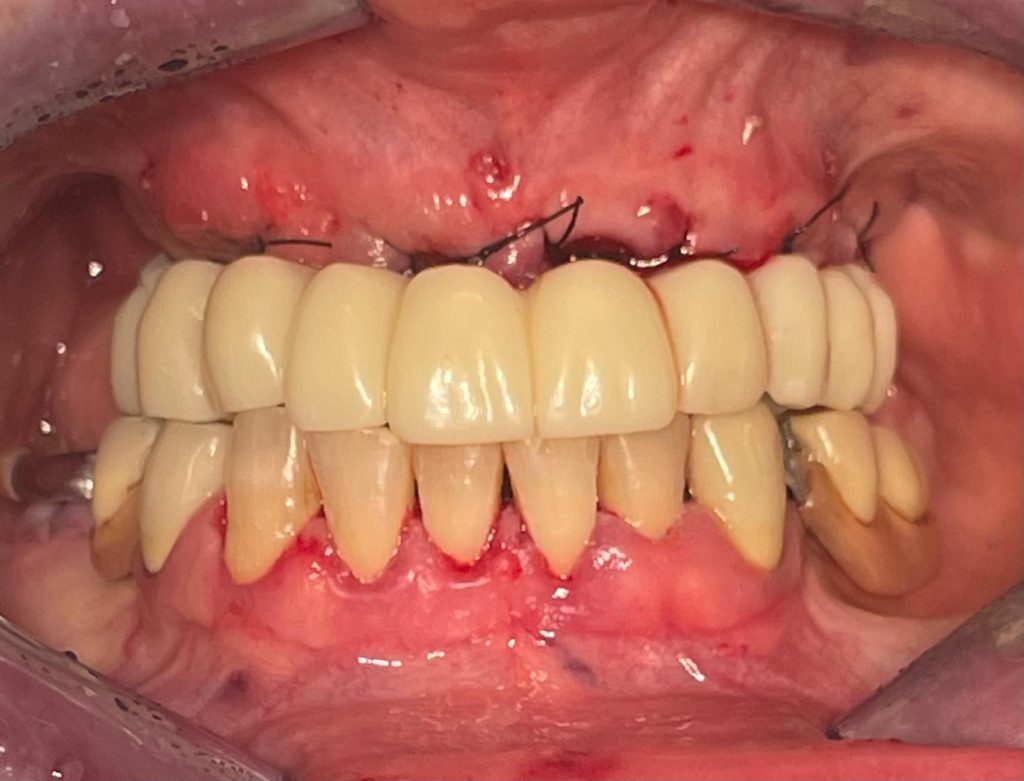

Questa settimana vi presento un caso di riabilitazione immediata dell’arcata superiore eseguita in chirurgia computer guidata con l’utilizzo di dime scomponibili.

L’intervento ha previsto l’estrazione degli elementi dentari, l’inserimento di 5 impianti nell’arcata superiore, il montaggio delle torrette provvisorie e la ribasatura del provvisorio nel cavo orale.